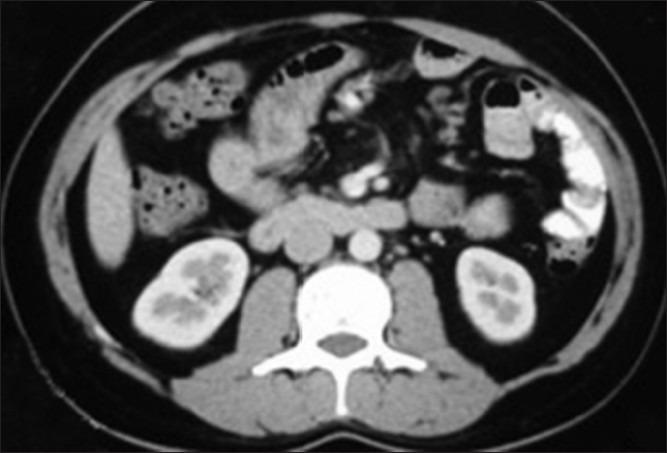

机器人辅助腹腔镜下睾丸肿瘤腹膜后淋巴结清扫术

Robot assisted laparoscopic retroperitoneal lymph node dissection in testicular tumor.

The treatment options in clinical stage I nonseminomatous germ cell tumor (NSGCT) of testis are either surveillance, chemotherapy or retroperitoneal lymph node dissection (RPLND). While open RPLND still serves as the gold standard, laparoscopic and robot assisted laparoscopic approaches are gaining popularity. In this report, we share our experience and technique of robot assisted laparoscopic RPLND in a patient with clinical stage Ib NSGCT of testis.

摘要